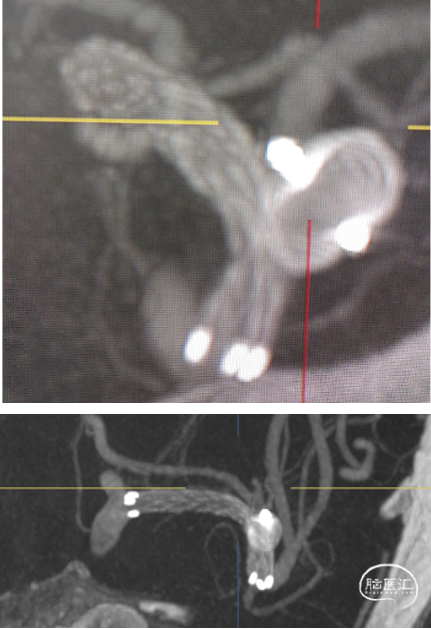

微导管3D评估动脉瘤与载瘤动脉关系

WEB选择:理想SL9x3(没有),选择SL8x4

直接测量:7.4x3.92mm

3D测量:7.22x5.35mm

对比测量:8.9x4.8mm(偏大10%)

微导丝支撑和保护下WEB释放

近端瘤颈残留,web按摩贴壁

按摩后瘤颈近端内漏消失!